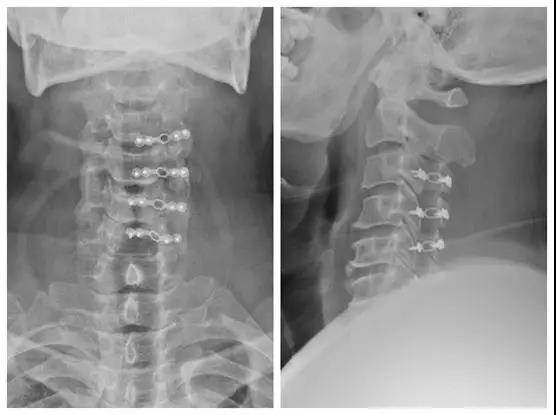

颈椎后路椎板切除减压,C3-6侧块螺钉、C2椎弓根螺钉固定,植骨融合手术

术中完成减压后置入钉棒系统

术中C臂透视